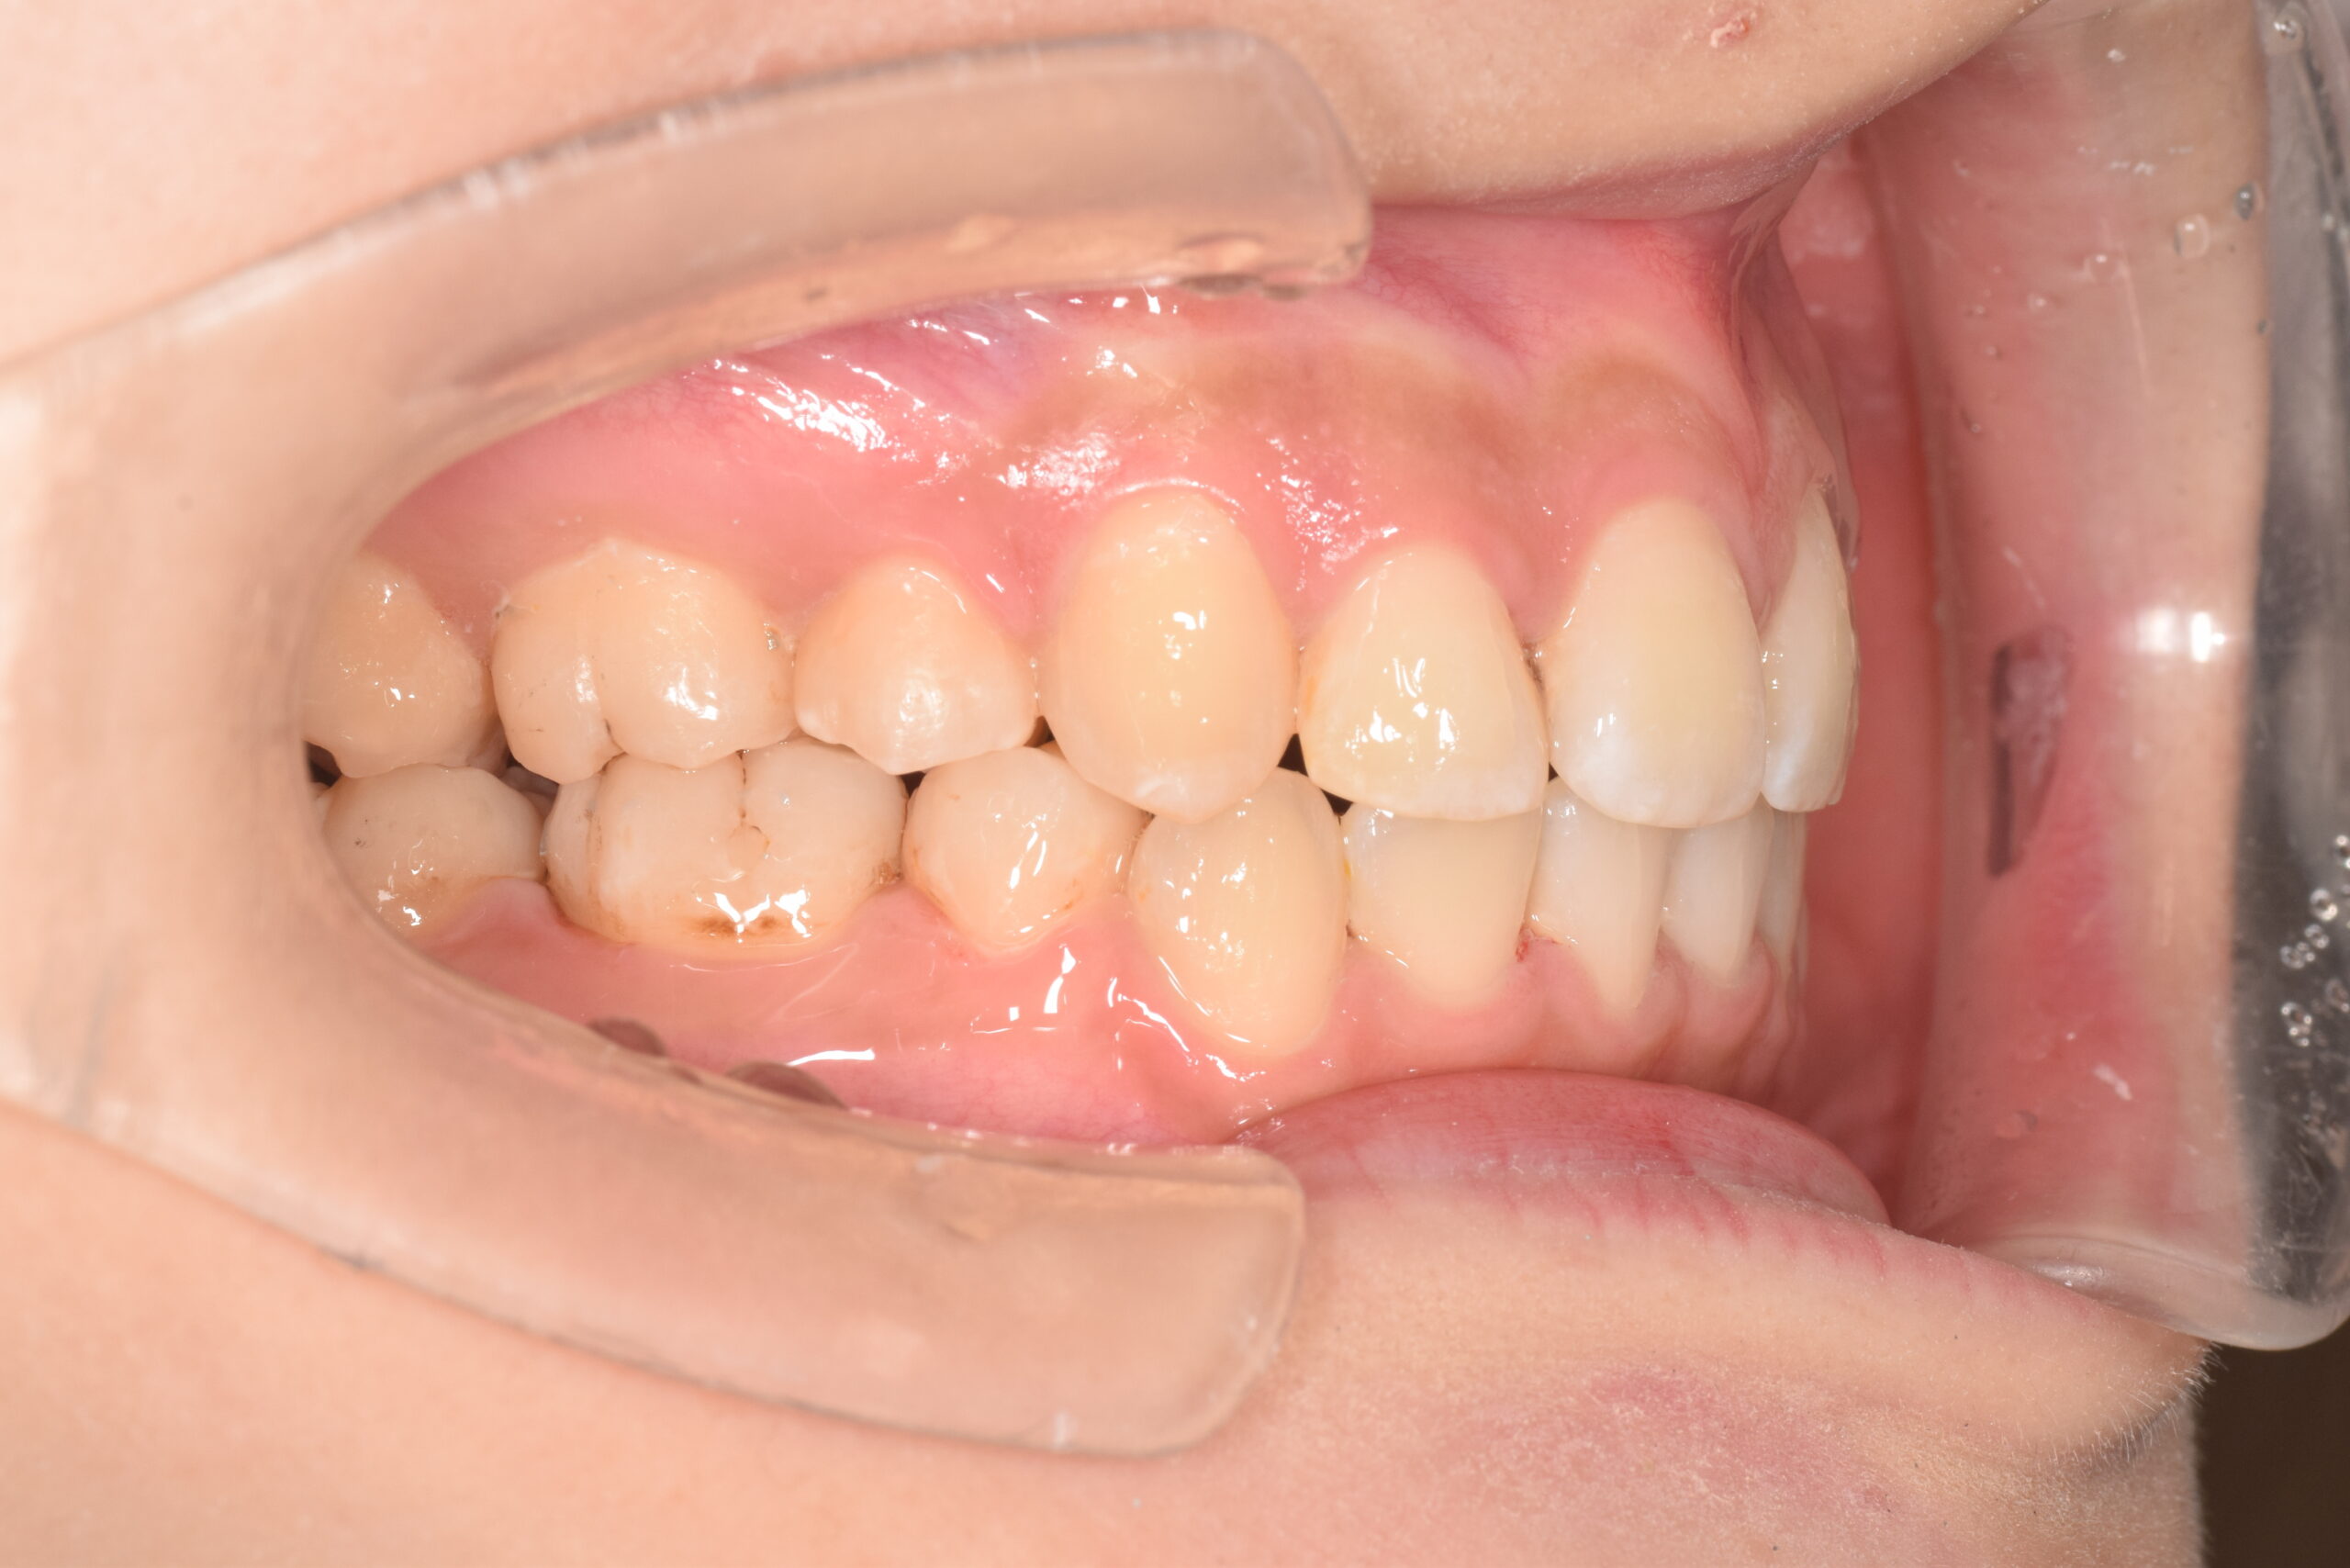

AFTER

| 年齢 | 19歳 |

|---|---|

| 主訴 | ガタガタが気になる |

| 症状 | 過蓋咬合を伴う叢生症例 |

| 治療内容 | 過蓋咬合を伴う叢生症例と診断し上下顎両側第一小臼歯の抜歯を行い、マルチブラケット装置を用いて治療を行いました。上顎は裏側の矯正装置、下顎は表側の矯正装置で治療を行いました。ハーフリンガル矯正治療。 |

| 抜歯部位 | 上下顎両側第一小臼歯 |

| 治療期間 | 3年 |

| 費用(税込) | 1,045,000(税込)別途処置料 |

| 治療のリスク | 虫歯、歯周病の悪化、歯肉退縮、歯根吸収、顎関節症の悪化、後戻り |